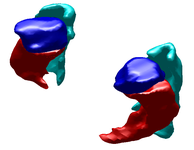

Left Atrium Segmentation for Atrial Fibrillation TreatmentThe planning and evaluation of left atrial ablation procedures is commonly based on the segmentation of the left atrium, which is a challenging task due to large anatomical variations. In this paper, we propose an automatic approach for segmenting the left atrium from magnetic resonance imagery (MRI). The segmentation problem is formulated as a problem in variational region growing. In particular, the method starts locally by searching for a seed region of the left atrium from a given MR slice. A global constraint is imposed by applying a shape prior to the left atrium represented by Zernike moments. The overall growing process is guided by the robust statistics of intensities from the seed region along with the shape prior to capture the whole atrial region. More... New: L. Zhu, Y. Gao, A. Yezzi, A. Tannenbaum. Automatic Left Atrial Segmentation from MRI images using Variational Region Growing with a Shape Prior, IEEE Transaction on Medical Imaging(TMI), in submission. New: L. Zhu, Y. Gao, A. Yezzi, R. MacLeod, J. Cates, A. Tannenbaum. Automatic Segmentation of the Left Atrium from MRI Images Using Salient Feature and Contour Evolution, IEEE Engineering in Medicine and Biology Conference(EMBC), 2012. |

Ventricles Segmentation for Diagnosis of Cardiac DiseasesThis work presents an automatic method for extracting the myocardial wall of the left and right ventricles from cardiac CT images. In the method, the left and right ven- tricles are located sequentially, in which each ventricle is detected by first identifying the endocardial surface and then segmenting the epicardial surface. More... New: L. Zhu, Y. Gao, V. Appia, A. Yezzi, C. Arepalli, T. Faber, A. Stillman, A. Tannenbaum. A Complete System for Automatic Segmentation of Left Ventricular Myocardium from CT Images using Shape Decomposition and Contour Evolution, IEEE Transaction on Image Processing(TIP), in submission. |